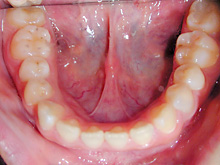

下顎前歯の叢生の改善のために部分矯正を希望されました。下顎の前歯群には中等度の叢生がみられます。

神経系の慢性疾患のためお薬の副作用の影響で歯肉の腫脹が目立っています。

下顎前歯の叢生の改善するためには上下顎前歯の接触が緊密なために上顎の前歯の矯正治療が必要となります。

臼歯関係、犬歯関係ともに1対2歯でよく咬んでいますので

咬み合わせの関係を壊すことなく上下顎の前歯の叢生を部分矯正で改善をめざします。

側貌から口元には緊張がなく突出を認めなかったので非抜歯で矯正治療できると患者様にはお伝えしました。

薬物の副作用の影響の歯肉の腫れは叢生の改善によりブラッシングが容易になると改善されることを期待します。

上下顎の前歯を前方へ移動させ、その状態により前歯のストリッピングを行うなどを計画します。